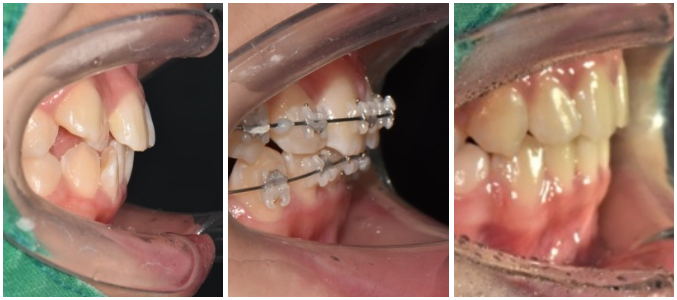

전 – 중 – 후

뻗쳐 있던 앞니도 긴밀하게 배열이 됨에 따라

자연스레 개선이 된 것을 확인할 수 있네요.

이후 망우동 치과 에서는

전처럼 돌아가려는 성질을 막기 위해

고정식 유지 장치를 부착한 뒤 마무리를 도왔습니다^^